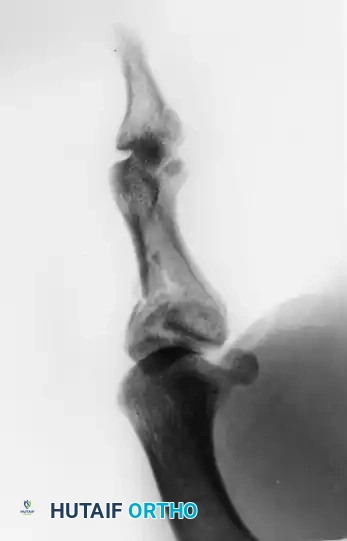

FIGURE 67-19 A and B: Preoperative anteroposterior and lateral radiographs demonstrating a highly comminuted, displaced intra-articular fracture of the base of the thumb proximal phalanx in a young male patient.

FIGURE 67-19 E and F: Postoperative radiographs confirming anatomical fracture fixation with simple, crossed Kirschner wires.